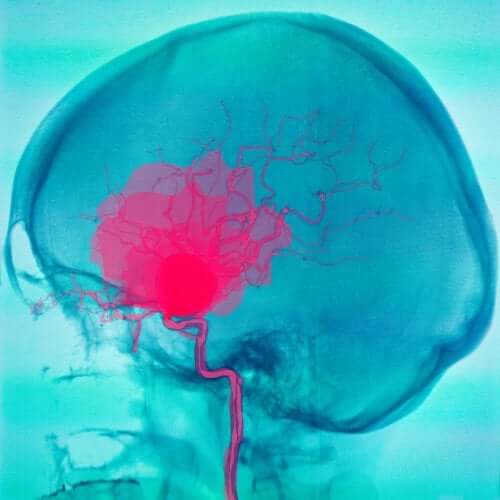

L’hémorragie sous-arachnoïdienne

L’hémorragie sous-arachnoïdienne correspond à un noyau de sang qui se trouve entre l’arachnoïde et la pie-mère. Le sang est généralement d’origine artérielle et différentes causes peuvent expliquer sa présence.

La cause la plus fréquente est une rupture d’anévrisme. Les malformation vasculaires peuvent constituer une autre raison.